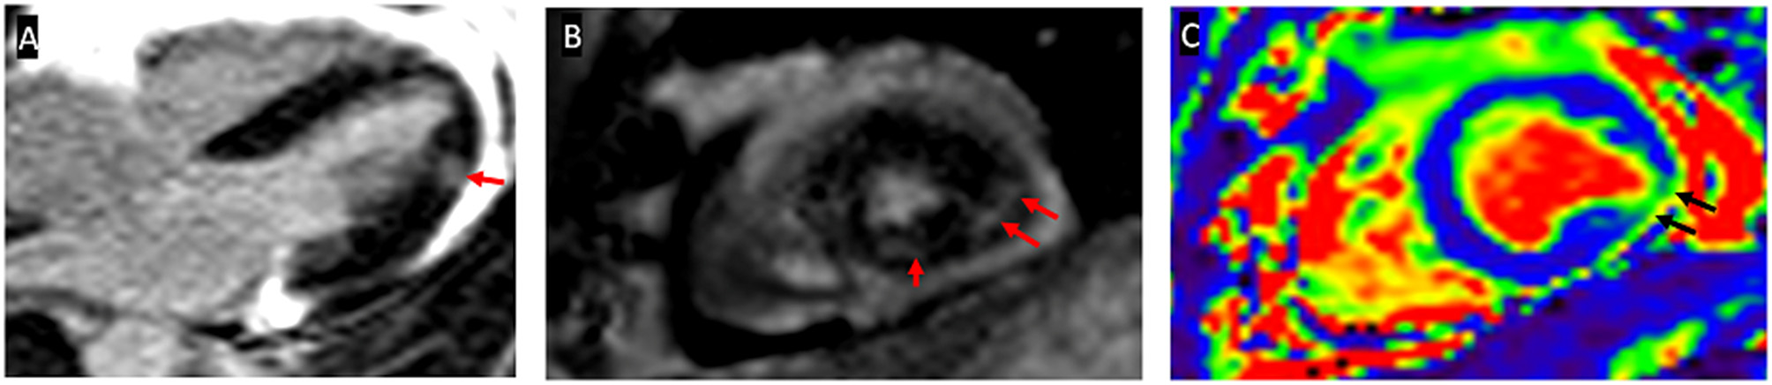

The first patient had an asymptomatic elevation of cardiac biomarkers. C-MRI showed myocardial edema in T2 mapping and LGE in a non-coronary distribution (Figure 2). Endomyocardial biopsies were performed according to C-MRI abnormalities and found non-specific edema. This patient was classified as having definite myocarditis because of increased cardiac biomarkers, positive C-MRI, and negative coronary angiography (13). The second patient was classified as possible myocarditis because of asymptomatic elevation of cardiac biomarkers, with negative C-MRI and angiography for coronary artery disease (13). In addition, the third case was classified as having definite myocarditis because of asymptomatic elevation of cardiac biomarkers, positive C-MRI but negative angiography for coronary artery disease (Table 3) (13).

Figure 2

Cardiac magnetic resonance imaging (C-MRI) imaging illustration of patient 1. (A) 4 cavity sections with a late enhancement of gadolinium and (B) transversal section showing infero-latero-medial mesomyocardic contrast (red arrows). (C) T2 mapping showing focal infero-latero-medial myocardial edema (black arrows).